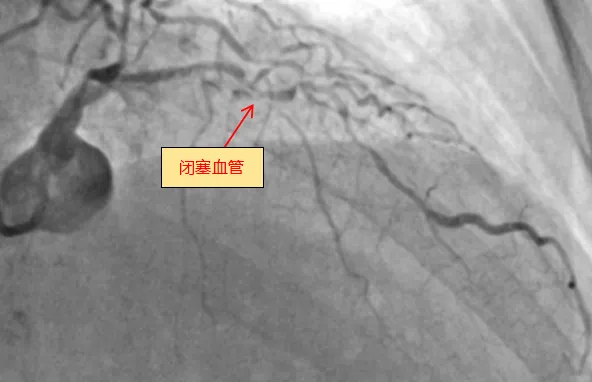

6月13日,老虎机app (简称老虎机app )心血管内科团队成功完成全新ROTAPRO™旋磨介入治疗系统上市后在广西的首次应用,为一名复杂高危严重钙化患者进行了精准冠脉介入治疗,顺利开通闭塞的冠脉血管并完成支架植入。71岁的梁阿姨(化名)去年外院冠脉造影诊断为冠心病,三支血管严重狭窄,于右冠植入一枚支架,前降支严重钙化病变尝试开通失败。近几个月来,她反复出现胸痛症状...